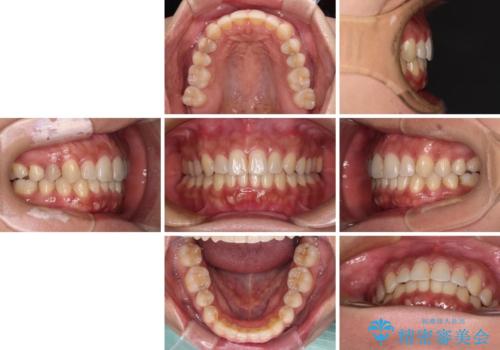

沖縄から飛行機で通院 インビザラインによる矯正治療

- 患者様

- 30代女性

- 矯正装置

- インビザライン

- 治療期間

- 3年8ヶ月

- 定期的に東京に来るので、沖縄から矯正治療で通院したいとのことで来院された患者様です。

歯列不正は軽度であったので、応急処置の少ないインビザラインにて矯正治療を行うこととしました。

- 治療費の目安: 85万円(税込)費用は治療当時の料金となります

通院途中に、仕事の都合で東京に来る機会が激減してしまったため、なかなか治療が進まず、当初終了予定であった時期が2年近くずれ込んでしまいました。

今後もむし歯治療が必要となるため、日程を調整して沖縄から通院されるとのことでした。